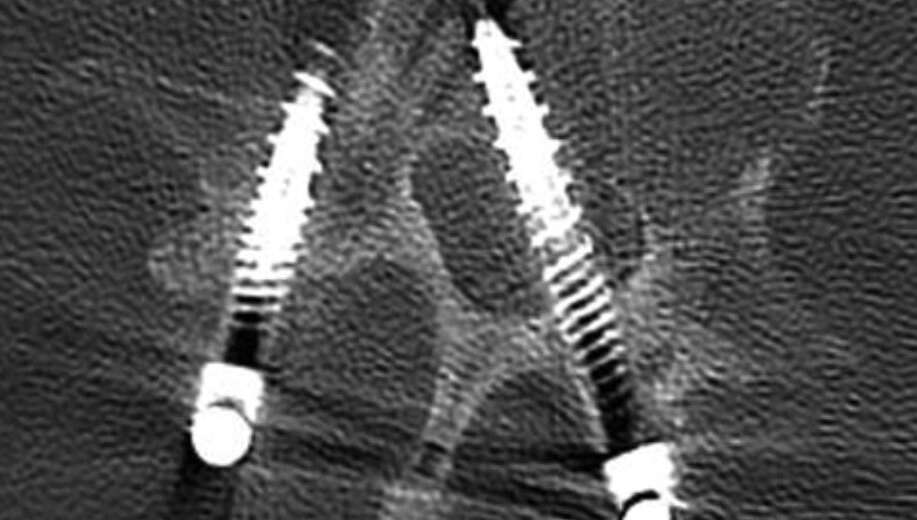

seecure sense is a smart instrument that supports Freehand or complements CAS systems for pedicle screw placement—delivering advanced predictive safety, lower radiation, and faster workflows across all generations..

At the core of seecure sense is Diffuse Reflectance Spectroscopy (DRS) — a proven optical technology. It works by sending a tiny pulse of safe light into tissue. The light bounces back differently depending on whether it hits spongy cancellous bone (high fat content) or hard cortical bone (high collagen content).

These reflected “signatures” are analyzed in real time, giving the surgeon an immediate readout of exactly where the instrument tip is—from safe cancellous zones through warning pre-cortical zones to dangerous cortical boundaries and potential breaches.

• seecure sense is the only system that gives surgeons “2 mm of vision beyond the tip.”

• This unique look-ahead distance combines tissue-level sensing accuracy with advance warning, so the surgeon knows not only where they are but also what lies ahead. The result is predictive safety — real foresight that helps avoid breaches and protect nerves, vessels, and the canal.